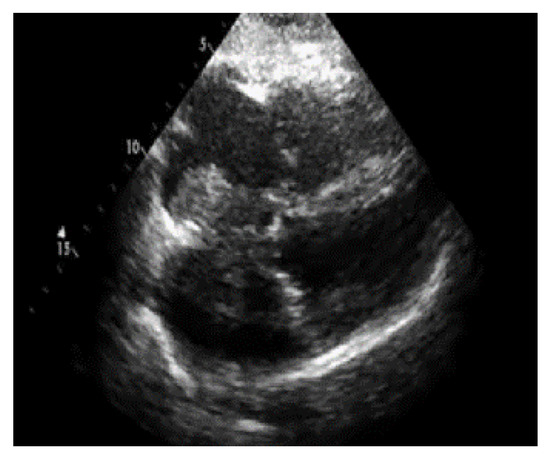

The numerical outcomes of the proposed as well as existing techniques are presented in this section. The input image of echocardiograms is given in Figure 4, and the pre-processed image is given in Figure 5. The FCM based segmentation is accomplished in echo images that is illustrated in Figure 6.

Figure 5.

Output of the pre-processed image.